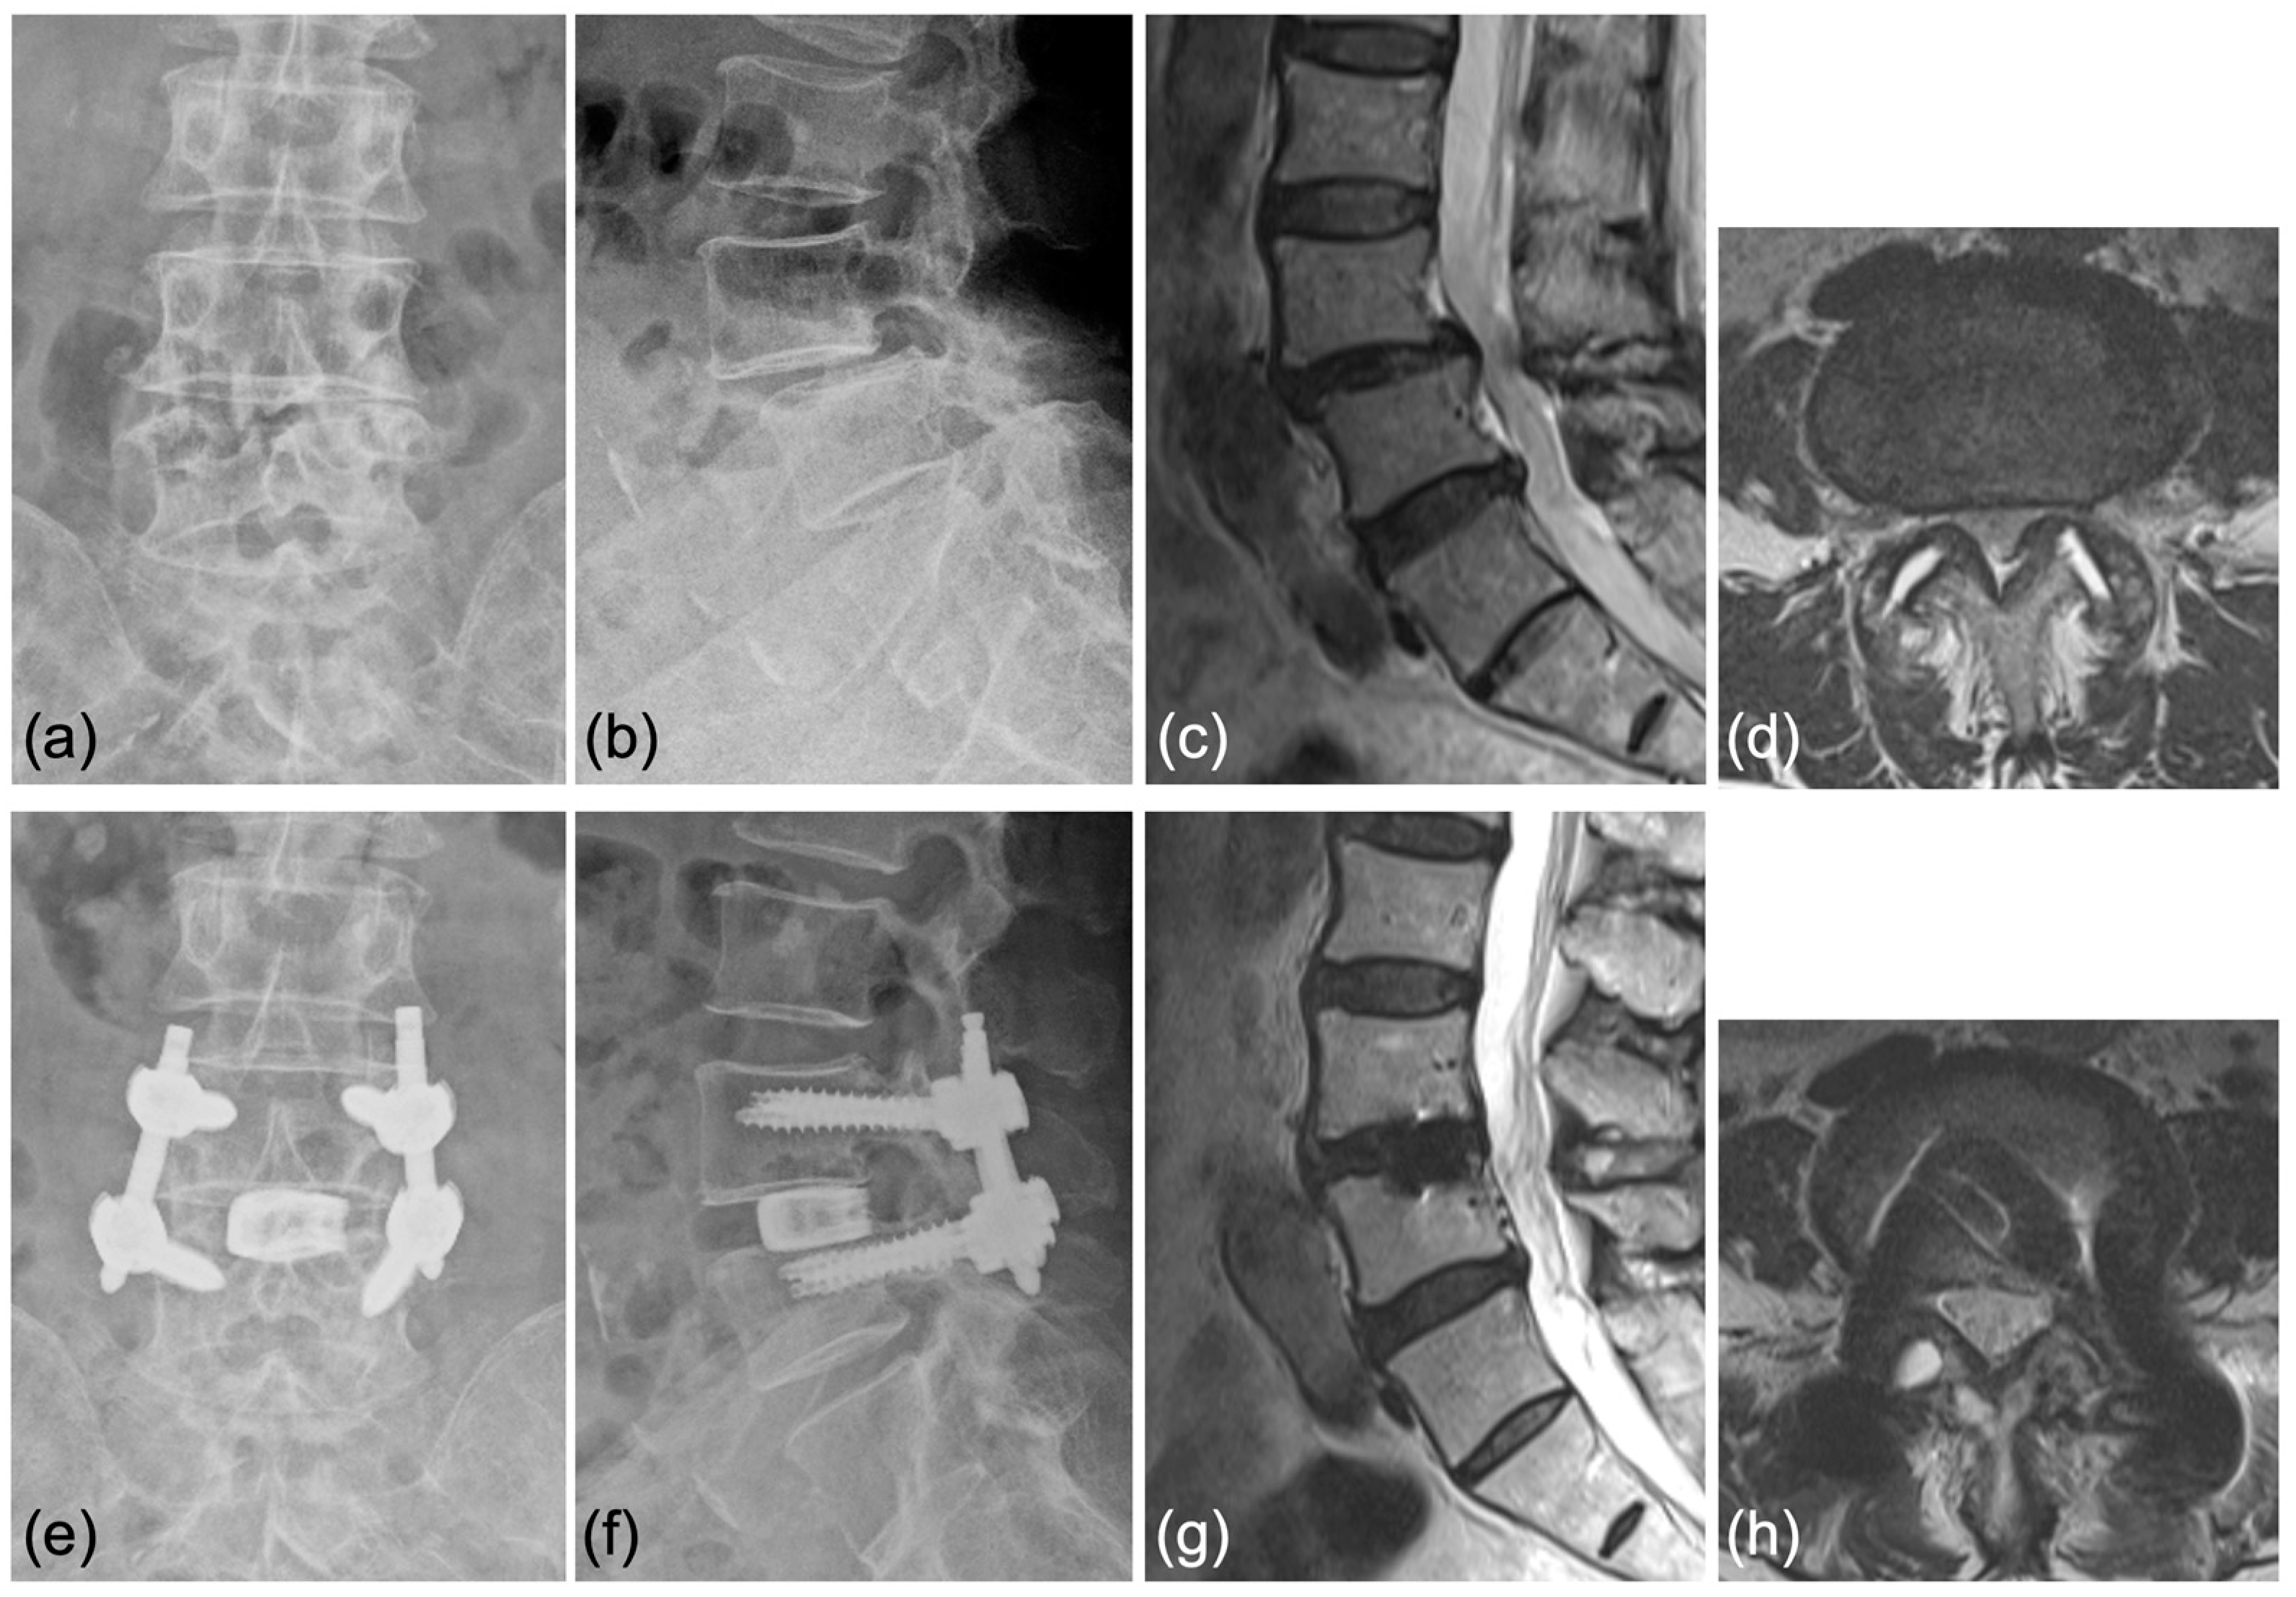

Case 1: A 70-year-old woman was diagnosed with degenerative spondylolisthesis of the L4 vertebra with instability by X-ray, CT, and MRI. VAS for back and leg pain were 100 and 60 mm, and the JOA score was 18/29. The spinal canal area was 95 mm2 at L4/5 disc level, and the % slip was 21% (Figure 7a–d). After the failure of conservative treatment, PETLIF was performed. One month after surgery, VAS back and leg pain improved significantly to 0 and 10 mm. Postoperative X-ray and MRI showed that the % slip was 0%, and the spinal canal area was expanded to 153 mm2 (Figure 7e–h). Bone fusion of L4/5 was confirmed by X-ray and CT scan one year after the surgery (Figure 8a–d).

(a,b) Preoperative X-ray showing 2° L4 spondylolisthesis. (c,d) Preoperative MRI showed lumbar spinal stenosis at the L4/5 level. (e,f) Postoperative X-ray showed L4 spondylolisthesis was reduced to 0%. (g,h) Postoperative MRI showed the spinal canal area was expanded.